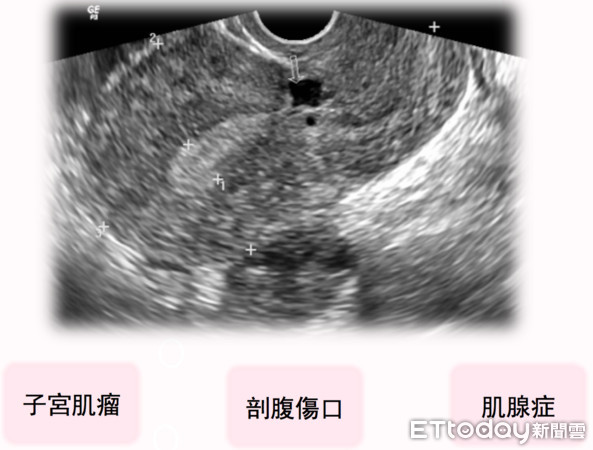

▲造成彭小姐續發性不孕症的原因。(圖/三總提供)

三軍總醫院婦產部婦瘤科主任王毓淇提到,彭小姐因第一胎剖腹產傷口未養好,才會導致續發性不孕症。檢查發現,彭小姐除了腸沾黏,子宮還有一顆直徑7至8公分大的肌瘤,醫療團隊先透過達文西手術修補傷口,術後2天就出院,胚胎解凍植入後也順利著床,隔年終於迎來第二胎。